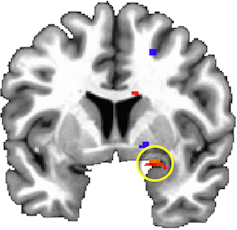

The association between media exposure and post-trauamtic stress symptoms was strongest for those with a particular brain response in the amygdala, a brain area involved in processing fear and detecting potential threats.

Earlier in the study, many of the same children had been particularly reactive when viewing fearful facial expressions. At the same time, their brain scans showed reduced activity in another region of the brain, the orbitofrontal cortex, thought to be involved in reducing emotional arousal.

That brain activation profile marked vulnerability for developing post-traumatic stress symptoms after viewing disaster-related media coverage.